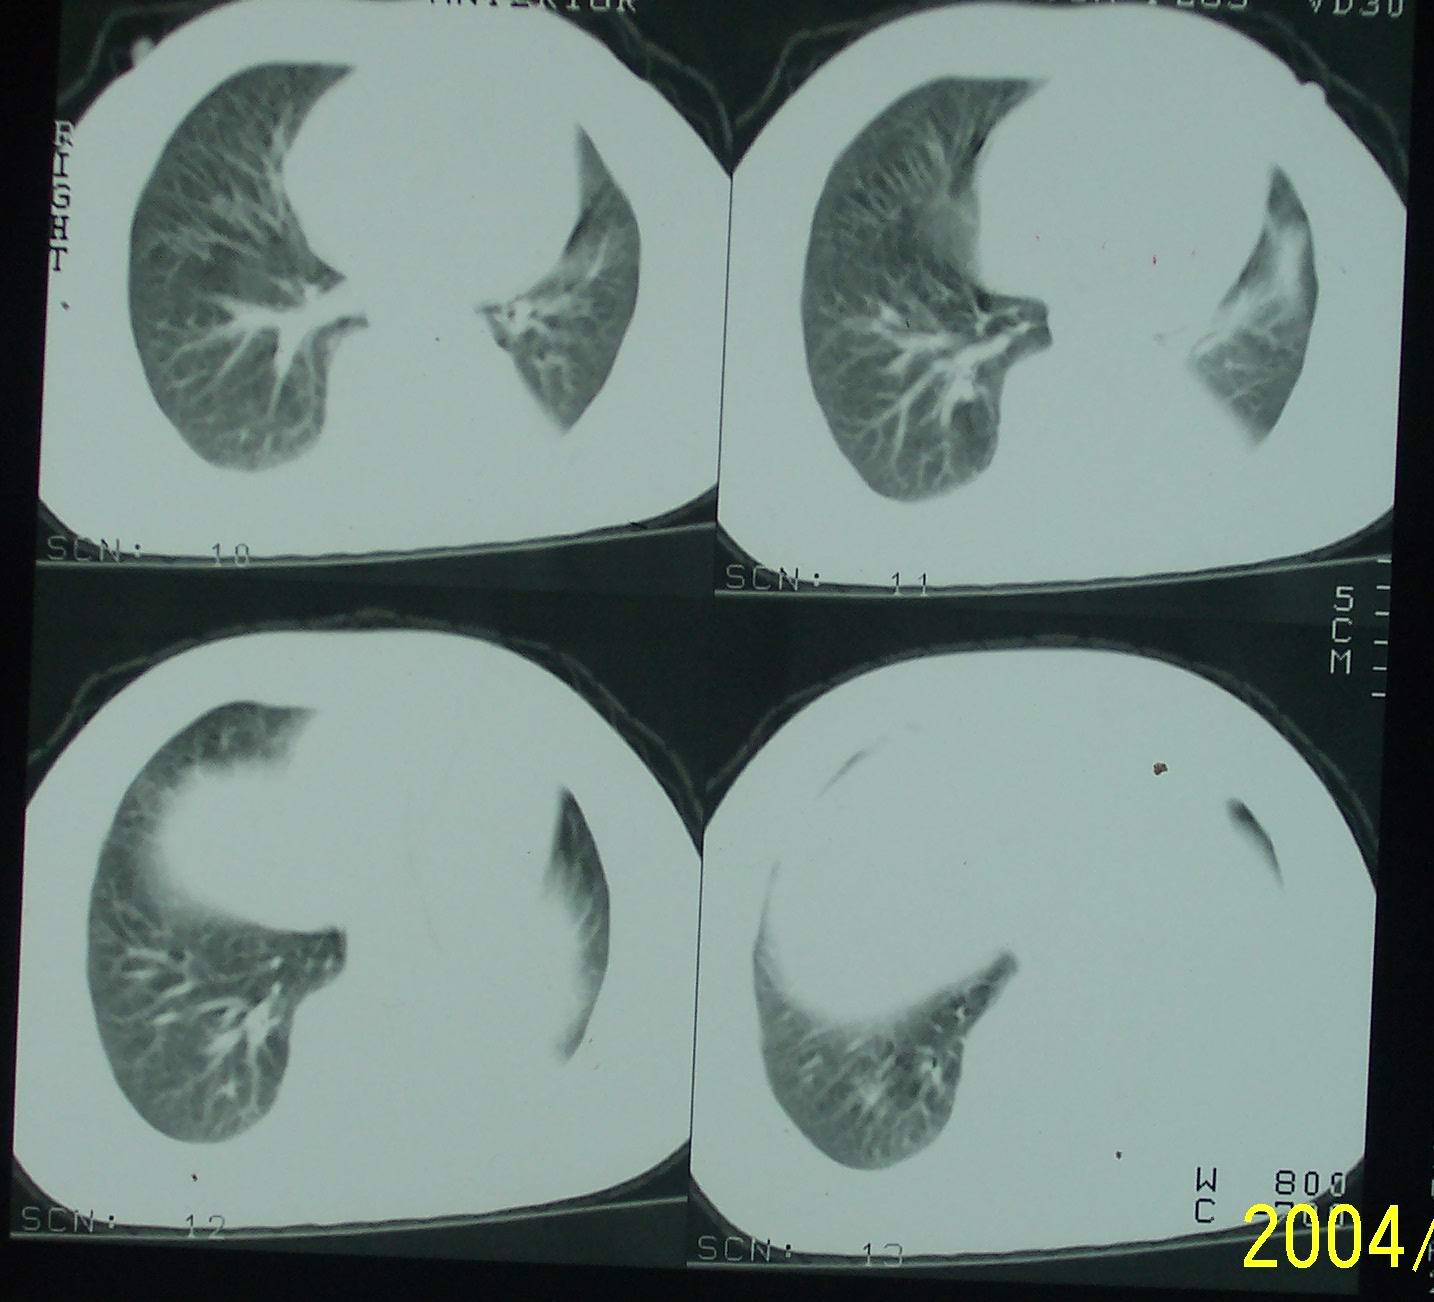

53岁女性,间断性腰部困疼、乏力一年,活动时加重。

左肺下叶后基底段片状实变影,密度均匀,左肺体积缩小,膈肌上提.考虑:左下肺肺不张.

1.左侧胸腔无明显萎陷,肺体积缩小,含气量减少,纵隔心脏左移。从这个意义来讲,左下肺病灶应该首先考虑肺不张。

2.左下肺病灶密度太过均匀,边缘过于光整锐利,位置特殊,其次应该考虑隔离肺的可能。

3.连续观察不能完全否定病灶是疝入胸腔的脾脏(扫描不怎么规范,跨越过大),所以膈疝也需要考虑。

补充一下病史:三天前因咳嗽咳血检查胸片见左下肺索条状影,后复查ct